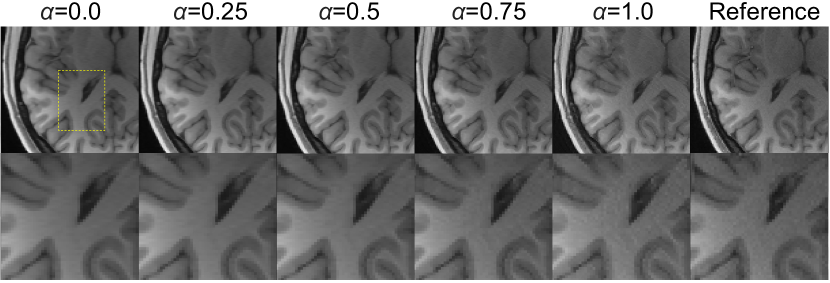

Fig. 5 illustrates the effect of model blending on the generated output image. The output varies smoothly with the interpolation factor α𝛼\alpha, allowing controllable trade off between reconstruction image and texture fidelity. Compared to blending model output images, mixing model parameters yields smoother results [18], and, equally important, is also more efficient since blending parameters requires minor computations and the generator only run once, while model output blending requires the generator to be run twice on two set of parameters.

Refer to caption

Figure 5: Sample image appearance as a function of blending between GAN oriented model (α=1𝛼1\alpha=1) and PSNR oriented model (α=0𝛼0\alpha=0), compared with ground truth.